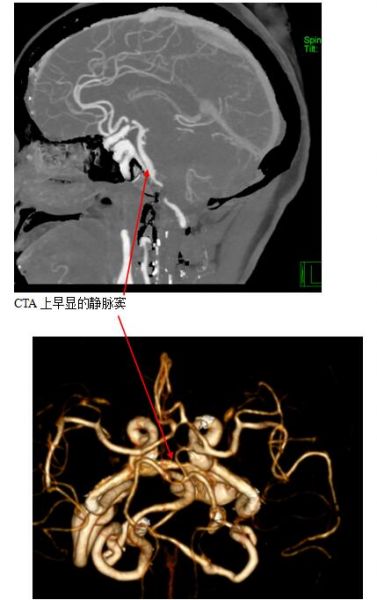

接到下级医师的请求,田勇副主任医师放下没有吃完的晚饭,立刻赶到病房,经过详细的询问病史及体查,认为左侧动眼神经麻痹诊断明确,患者没有明显发热,不太支持痛性眼肌麻痹,没有其他神经功能缺失,入院颅脑CT正常,不支持中脑梗塞,为了排除左侧后交通动脉瘤,田勇副主任医师直接赶往CT室,在CT室工作站仔细阅读分析,确实没有发现后交通动脉瘤,但凭借明锐的经验,发现了可疑的双侧海绵窦早显征象,高度怀疑海绵窦区的硬脑膜动静脉瘘,是一个比较少见的脑血管病变,没有经验的医生,很容易漏诊。

一旦怀疑DAVFs,神经内科一病区医生迅速和患者及家属沟通,及时完成脑血管造影,第一时间确诊患者为海绵窦区DAVFs(供血动脉为左侧颈内动脉海绵窦段,向左侧岩下窦及通过海绵间窦向对侧岩下窦引流)。